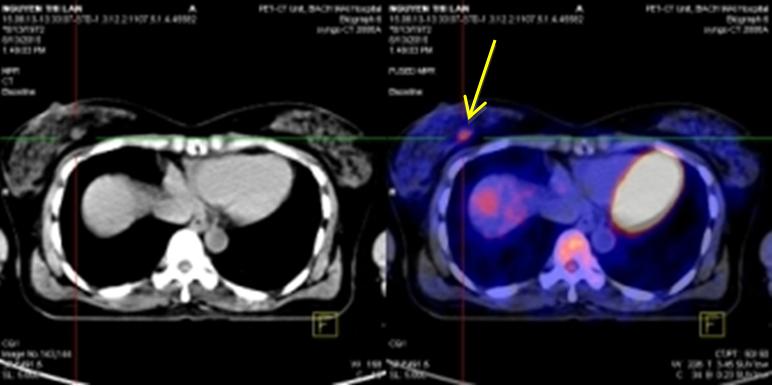

Kết quả chụp PET/CT:

Hình chụp PET/CT toàn thân

Nhân thùy phải tuyến giáp, kích thước: 1,4x1,0cm tăng hấp thu FDG, maxSUV=5,11. Nhân thùy trái tuyến giáp, kích thước: 1,9x1,6cm tăng hấp thu FDG, maxSUV=6,8.